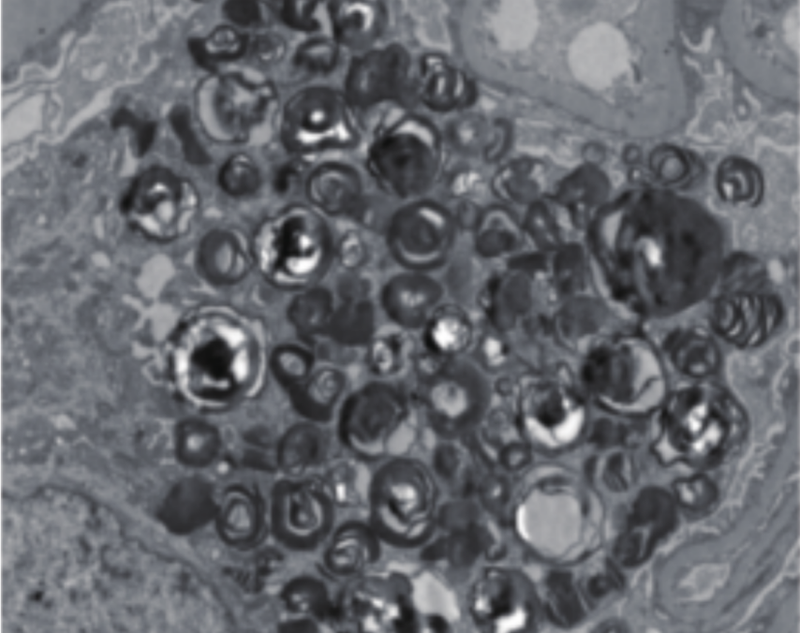

9歲男孩莫名其妙出現(xiàn)肢體疼痛,主要是手腳疼痛,發(fā)熱或劇烈運動時更為明顯。別人在曬太陽或者運動之后,都一身大汗,他卻不出汗,四肢都有灼燒感,還會發(fā)燒。了解到他媽媽和大姨小時候也有類似癥狀,成年后逐漸好了,這讓醫(yī)生懷疑到家族遺傳病。結合癥狀,醫(yī)生考慮到會不會是法布雷病,對他進行了α半乳糖苷酶(α-GalA)活性和基因的檢查,結果果然顯示酶活性顯著降低,GLA基因變異,證實了法布雷病的診斷。?法布雷病是一種罕見的溶酶體貯積癥,因為基因突變,導致身體里缺乏一種清除細胞內垃圾的酶——α半乳糖苷酶,造成細胞內堆積越來越多的垃圾,正常細胞就會被破壞,從而引起臟器的損害,當累及周圍神經(jīng),就會出現(xiàn)手腳痛、出汗障礙等。該病是一種X染色體連鎖遺傳病,由于女性有兩條X染色體,而男性只有一條X染色體,所以女性患者通常為雜合子,帶病基因被“稀釋”,發(fā)病時間相對較晚且臨床表現(xiàn)較輕,預期壽命減少約6-10年;而男性患者均為半合子,發(fā)病較早且大多出現(xiàn)經(jīng)典的臨床表現(xiàn),造成預期壽命減少約15-20年。通常,男性患者會將帶病的X染色體遺傳給女兒,兒子患病的概率為零。女性患者將異常X染色體遺傳給女兒和兒子的概率均為50%。法布雷病分為經(jīng)典型和遲發(fā)型。經(jīng)典型法布雷病:發(fā)病早,多見于男性,在青少年時期出現(xiàn)癥狀,表現(xiàn)為肢體末端燒灼樣疼痛、少汗/無汗、腹痛/腹瀉等,不能及時診斷治療,就會逐漸出現(xiàn)心、腎等重要臟器受累,心臟表現(xiàn)為心肌肥厚,心臟變大,但實際上是“虛胖”,心臟功能是下降的,出現(xiàn)疲乏、心慌、胸悶氣短,逐漸心臟衰竭,表現(xiàn)為夜間呼吸困難,必須坐起后才能緩解。腎臟損害表現(xiàn)為多尿、夜尿增加,隨著病情進展出現(xiàn)血尿、蛋白尿、水腫及腎功能受損,最后發(fā)展為尿毒癥。做腎臟活檢時,如果做電子顯微鏡檢查,可發(fā)現(xiàn)典型的病理特征——斑馬小體。這就是細胞內堆積了太多的垃圾造成的表現(xiàn)。遲發(fā)型法布雷?。憾嘁娪谂裕猿赡旰蟀l(fā)病為主,主要表現(xiàn)為心、腎受累。法布雷病如何確診?篩查法布雷病并不難,干血紙片法(DBS)就是一種簡便、快捷的方法。醫(yī)生采血滴在干制片上,寄到檢測中心就可以檢測α-GalA酶的活性。男性患者α-GalA活性正??苫九懦ú祭撞?,酶活性下降的患者則需要接受基因檢測。女性患者α-GalA酶活性可能是正常的,需要結合基因檢測等綜合評估來確診。法布雷病的治療核心在于補充缺失或不足的酶(α-GalA)。酶替代治療,即定期補充人工合成的α-GalA酶,替代體內缺陷的酶,已經(jīng)成功用于臨床?;蛑委煼椒ㄒ惨呀?jīng)成功開展了臨床研究,這一方法是把患者所缺陷的基因搭載在腺病毒上,腺病毒帶著這段基因感染患者,把它整合進患者自己的基因中去,從而彌補基因缺陷。女性法布雷病患者或攜帶者在生育時,可以到有條件做第三代試管嬰兒的生殖中心,進行胚胎植入前單基因病遺傳學篩查(PGT-M)干預,從而阻斷致病基因的遺傳。法布雷病如果未能及時有效治療,往往導致過早死亡,預期壽命可減少數(shù)十年。因此,早診早治是關鍵。當一個患者被診斷出法布雷病時,鑒于法布雷病是一種X連鎖遺傳病,其男性和女性親屬都有患有法布雷病的可能,他們可能正被各種疾病困擾,卻不知道自己到底患了什么病。另外,還存在很多“遲發(fā)型”法布雷患者,雖然目前的生活和常人無異,但是大多在40歲后,出現(xiàn)心臟、腎臟、腦/神經(jīng)系統(tǒng)的損傷。如果沒有早診早治,也會造成不可挽回的后果。國外家系篩查的數(shù)據(jù)顯示,圍繞一名最先被確診的患者,平均有5名家庭成員被診斷出患有法布雷病。所以,確診一名法布雷病患者,對所有家族成員都應進行篩查。確診后,有些可以先監(jiān)測暫不治療,有些需要及時開展酶替代療法,以避免更嚴重的臟器損害的后果。